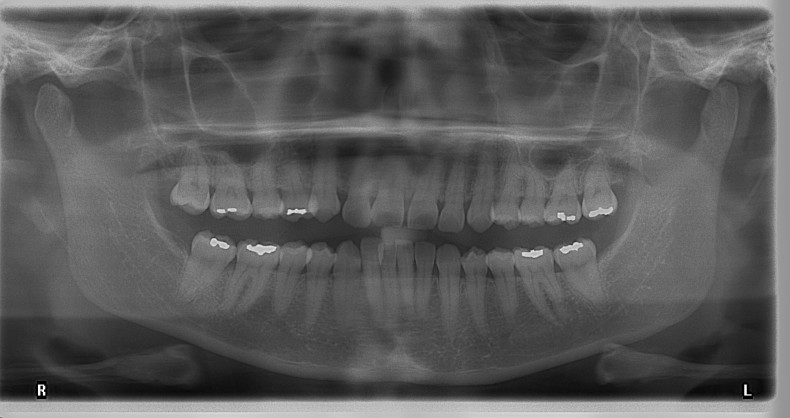

Die FRS-Auswertung (Abb. 1d) ergab eine distal-basale Kieferrelation nach WITS (2,6 mm) bei tendenzieller maxillärer Prognathie (SNA 86,5°). Aus der dentalen Analyse des FRS ging eine deutliche Anteinklination der Oberkieferinzisivi (IOK-NL 126,5°) und eine manifeste Anteinklination der Unterkieferinzisivi (IUK-ML 103,6°) bei stark verkleinertem Interinzisalwinkel (IOK-IUK 112,3°) hervor. Die vertikalen Parameter ergaben einen brachiofazialen Gesichtsschädelaufbau. Die Auswertung des OPG (Abb. 1e) zeigte eine adulte Dentition mit fehlenden dritten Molaren. Außerdem war eine extreme Mesialkrümmung der Wurzel 25 erkennbar. Es zeigte sich ein moderater generalisierter horizontaler Knochenabbau des Limbus alveolaris im Ober- und Unterkiefer von ca. 15 Prozent.